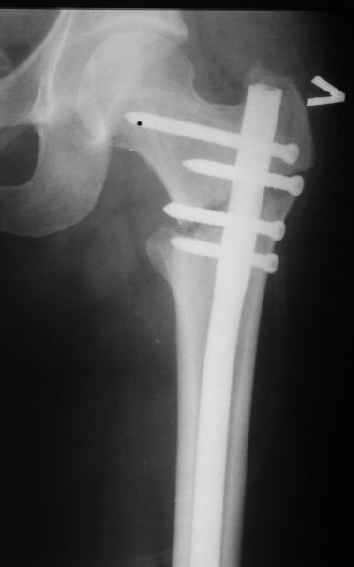

Могу скромно напомнить о существовании стержня нашей модификации.

В частности, на проксимальном конце сделано еще одно дополнительное статическое отверстие. Можно ввести в проксимальном отделе 4 винта, из них 3 статические (2 в круглые отверстия и 1 по нижнему краю овального). Картинки в приложении. На дистальном конце стержня тоже кое-что улучшено. Спрашивайте в аптеках, как говорится. Выпускается предприятием "ЦИТО" (Москва), то есть это малобюджетное решение.

Это было года 2,5 назад, мы тогда еще уточняли возможности шинирования с угловой стабильностью гвоздем с поперечным расположением винтов при переломах проксимального отдела бедра. Пациенту не пришлось приобретать намного более дорогой рекон или проксимальный гвоздь. В приложении еще несколько примеров применения того гвоздя при высоких переломах бедра, в том числе с более латеральной точкой входа. Гвоздь изгибаем для этого.